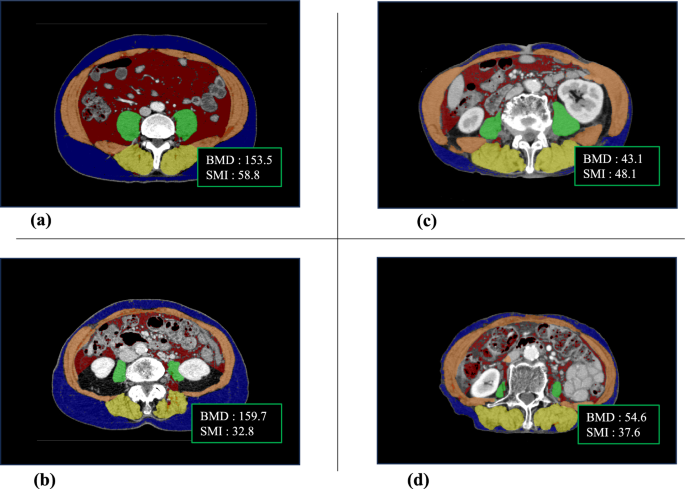

To enhance accuracy, both the SMI and BMD were measured at two points on the CT images and the average value was calculated. Figure 1 shows the representative CT images for a normal SMI and BMD range, sarcopenia, osteopenia, and osteosarcopenia.

Representative computed tomography images showing body composition ranges. Ranges of body composition include within normal (a), with sarcopenia—decreased skeletal muscle index (b), with osteopenia—decreased bone mineral density (c), and with osteosarcopenia—decreased skeletal muscle index and bone mineral density (d).